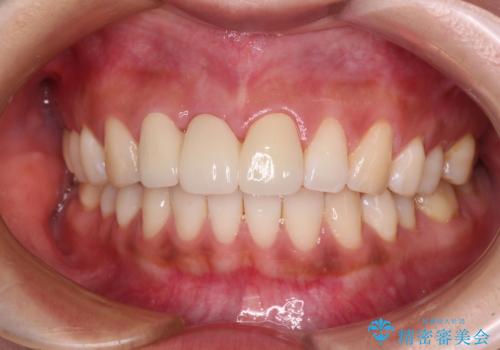

折れているのに応急処置でごまかしてきた前歯 オールセラミックブリッジによる補綴治療

抜歯による歯槽骨や歯肉が陥没して審美障害を起こすことがありますが、今回は仮歯でも違和感のない外観となったため、歯肉移植術を行うことなく仕上げることができました。